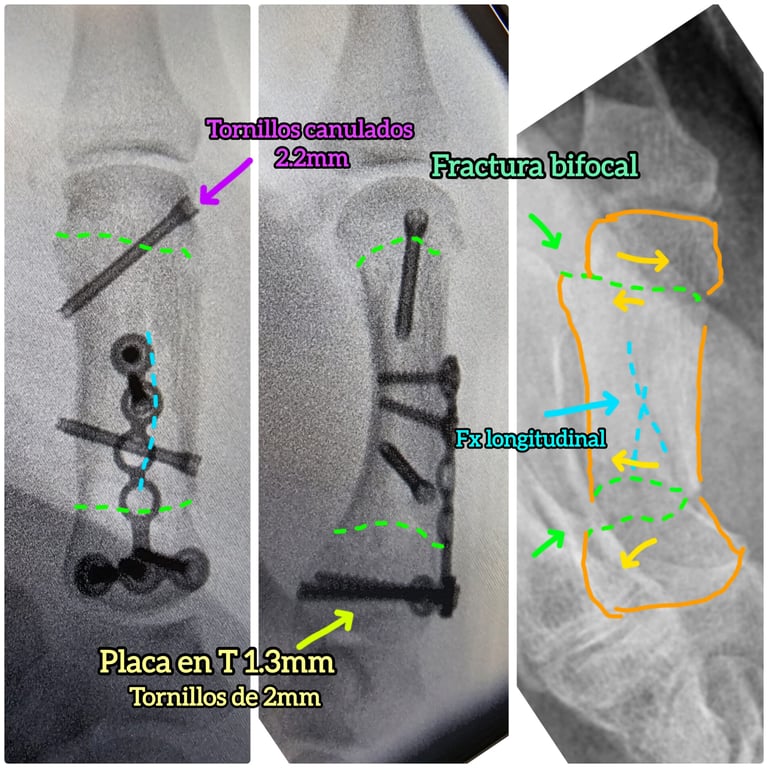

Radiografías para confirmar el tipo de fractura y su desplazamiento

En casos complejos puede ser necesario ampliar el estudio para planificar correctamente el tratamiento.

Desplazamiento significativo

Inestabilidad

Afectación articular

Deformidad o rotación del dedo

La cirugía busca restaurar la anatomía, permitiendo una movilización más precoz y una mejor recuperación funcional.